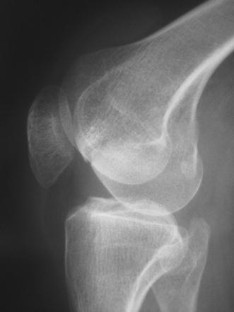

Fig. 1